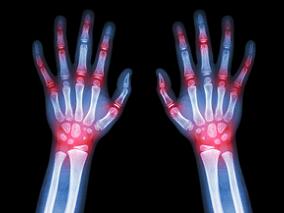

类风湿性关节炎:低剂量MTX+叶酸补充剂 细胞减少副…

1小时条评论甲氨蝶呤(MTX)是类风湿性关节炎治疗的基石药物,但其可导致细胞内叶酸缺乏,减少核蛋白合成,抑制细胞的增殖和复制。不过,2020年4月,发表在《Rheumatology (Oxford)》的一项随机对照临床试验的荟萃分析显示,类风湿性关节炎患者使用低剂量MTX联合叶酸补充剂,细...

类风湿性关节炎患者:托珠单抗vs依那西普的心血管安…

1小时条评论2020年1月,发表在《Arthritis Rheumatol》的一项研究显示,对于类风湿性关节炎(RA)患者,托珠单抗vs依那西普的主要不良心血管事件(MACE)风险相似。 目的:旨在评估在RA患者中,托珠单抗vs肿瘤坏死因子抑制剂依那西普的MACE风险。 方法:该项随机、开放标签、...

哪些类风湿性关节炎患者容易不依从甲氨蝶呤治疗?

1小时条评论甲氨蝶呤(MTX)是RA(类风湿性关节炎)患者的常规一线用药,但并非所有患者都能应答,用药不依从是原因之一。2020年 1月,发表在《Rheumatology (Oxford) 》的一项研究显示,患者个人意愿和多发病与不依从强烈相关。 目的:为了建立干预措施以优化MTX用于治疗RA,...